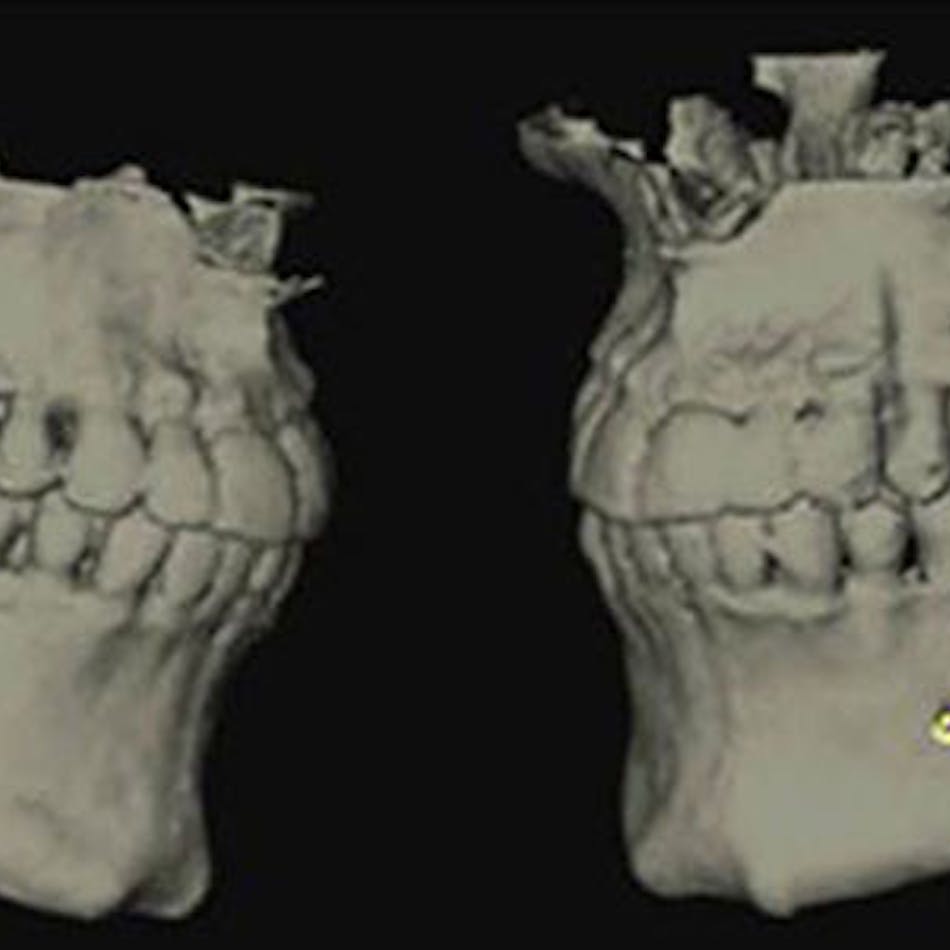

For example, one patient of a general dental practice had a caries-free history for 35 years. He ceased smoking traditional cigarettes and decided to vape as he thought this was a healthier alternative. Within a year, cervical enamel demineralization and interproximal lesions were present on the mandibular anterior sextant, consistent with the primary point of contact of the e-liquid aerosol (figure 2).

Figure 2: Effects of e-cigarette usage